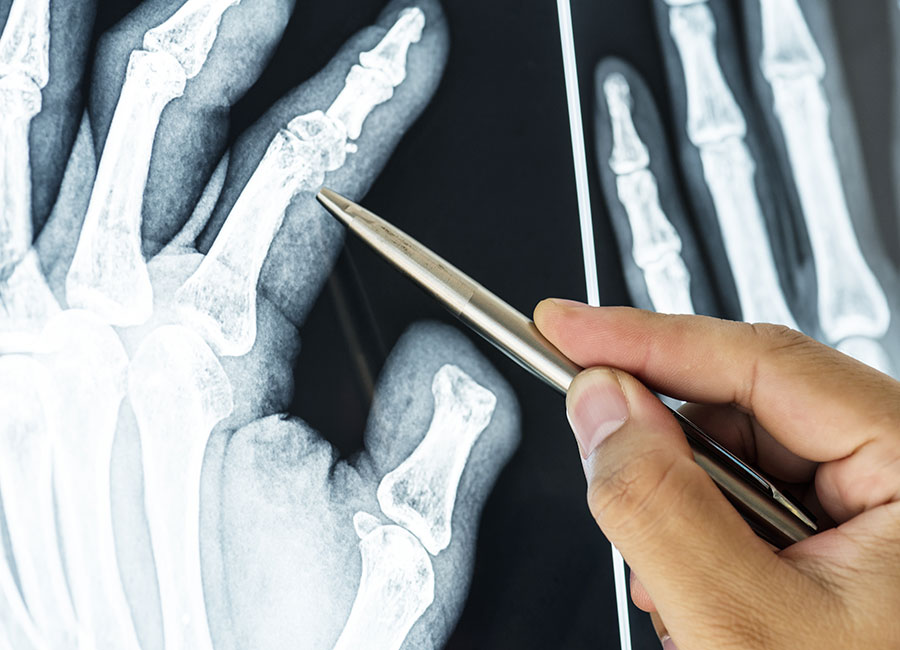

Chirurgia della mano

Trattamento chirurgico delle patologie e delle lesioni della mano e del polso, volto a preservare funzionalità, precisione e forza nei movimenti.